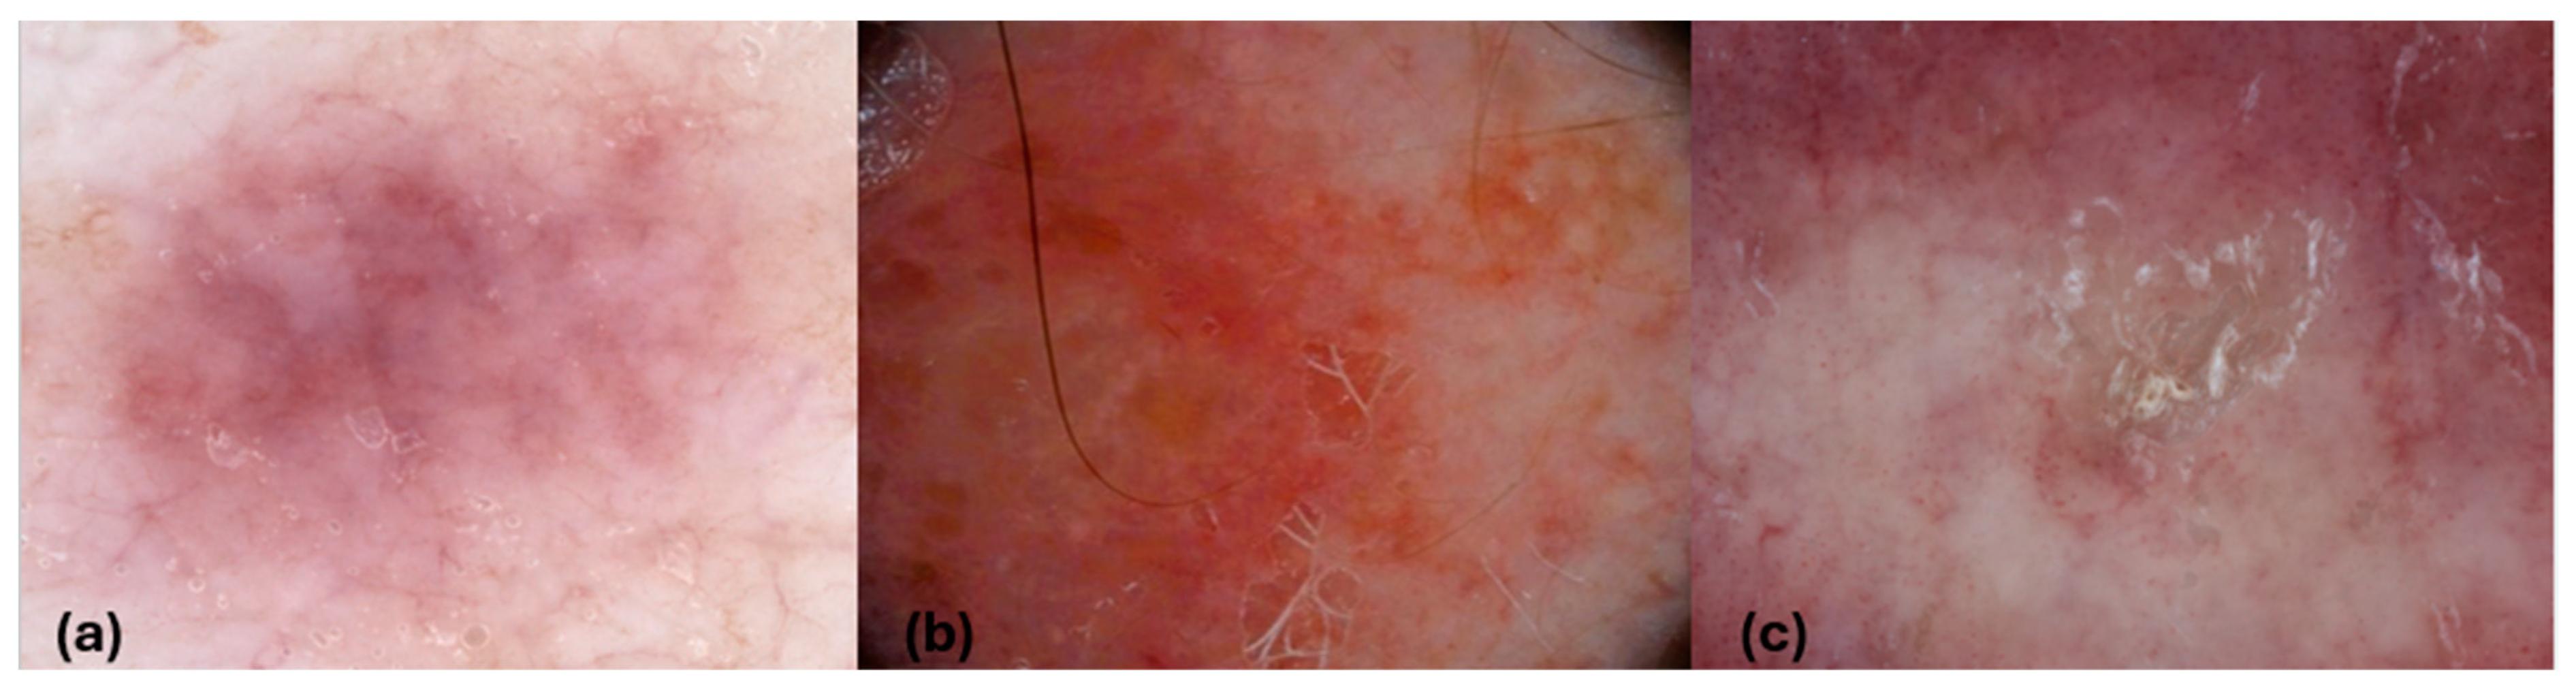

| Dermatoscopic Features | CBCL (n = 7) | CTCL (n = 29) |

|---|---|---|

| Vessels | ||

| Dotted | ||

| Uniform, n (%) | 0 | 10 (35.7) |

| Clustered, n (%) | 0 | 5 (17.9) |

| Linear, n (%) | 5 (71.4) | 4 (13.8) |

| Linear vessels with branches, n (%) | 2(28.5) | 0 |

| Linear curved (spermatozoa-like structures), n (%) | 0 | 7 (24.1) |

| White scale, n (%) | 1 (14.3) | 9 (31) |

| Yellow scale/crusts, n (%) | 0 | 2 (6.9) |

| White structureless patches, n (%) | 1 (14.4) | 3 (10.3) |

| Orange-yellow structureless areas, n (%) | 4 (57.1) | 0 |

| Bright red structureless areas, n (%) | 3 (42.9) | 2(6.9) |

| Pinkish structureless areas, n (%) | 2 (28.6) | 17 (58.6) |

| Ulceration, n (%) | 0 | 1 (3.4) |

| Shiny white structures (crystalline structures or chrysalis), n (%) | 3 (42.9) | 3 (10.3) |